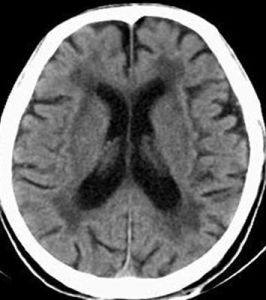

CT及MR(磁共振)等神經影像學檢查可發現腦組織體積減少、腦室擴大。如果大腦萎縮可見腦皮質與顱骨板間隙增大,大腦溝增寬增深、腦回變平縮小,側腦室及第三腦室擴大,側腦室前后角周圍密度減低。小腦萎縮時可顯示小腦腦溝增寬增深,體積縮小,影像呈現分枝樹葉狀,小腦周圍腔隙增大,第四腦室擴大。如果有橋腦橄欖體萎縮,在神經影像上可見腦幹變細狹窄,周圍腔隙增大、橄欖體變扁平或縮小。

科學研究表明,大腦最外層是呈灰色的大腦皮層,由140億個神經細胞體組成,厚3.5mm,大腦皮層表面曲折不平,有凹陷的腦溝和凸起的腦回,大腦皮層下面為白色的髓質。在腦的中部還有數個呈空隙的腦室。腦神經老化死亡後,腦的重量變輕,體積變小,CT檢查呈現腦體積縮小,腦溝變寬,腦回變細,腦室擴大,這就是腦萎縮。